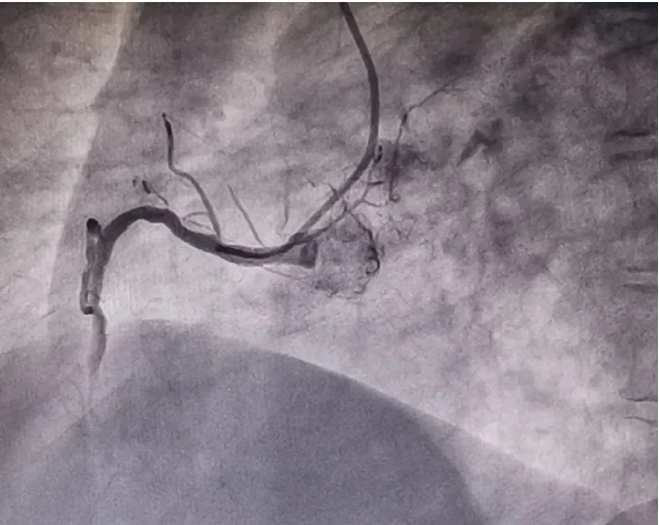

放射科、介入诊疗室、心血管科与急诊科紧急联动,迅速会诊,制定急性心肌梗死介入治疗手术方案,在冠脉造影检查过程中发现,患者右冠状动脉中断完全闭塞,病情十分危急!李友文主任医师迅速将导丝通过闭塞血管,并及时给予替罗非班血管注入,减轻血小板的聚集,抑制血栓形成,促进再灌注形成;球囊通过后给予后适应处理,防止再灌注心律失常的发生。整个手术过程顺利,成功为患者植入一枚支架,用时40分钟,患者术后恢复良好。